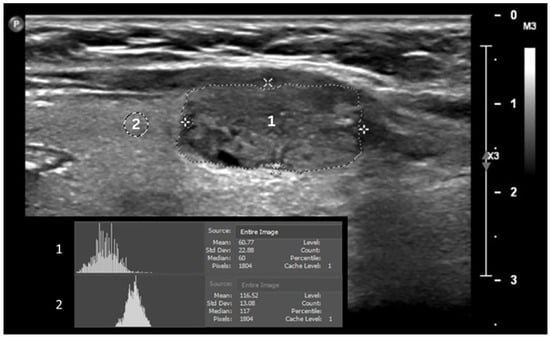

Artificial intelligence is emerging as a powerful new tool for tissue characterization from radiological images. Hence, its application in the diagnosis of cancer diseases is opening up new avenues that could broaden the spectrum of cancers that can be targeted earlier for therapy. From ultrasound to the most sophisticated MRI machines, these advances in imaging are driving changes that could revolutionize the way radiology is perceived.